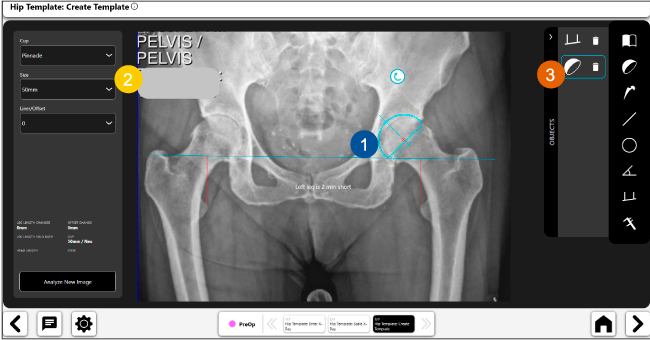

Planeación preoperatoria mediante la creación de plantillas digitales para reemplazo de cadera y análisis intraoperatorio

Disponibilidad de plantillas digitales de cadera.

Expediente histórico y personalizado, optimiza la planeación con el calendario de casos realizados en Velys TM y utiliza los íconos interactivos para una rápida revisión.

Espacio colaborativo: puede compartir los casos entre cirujanos y sus equipos mediante la funcionalidad de intercambio de información.